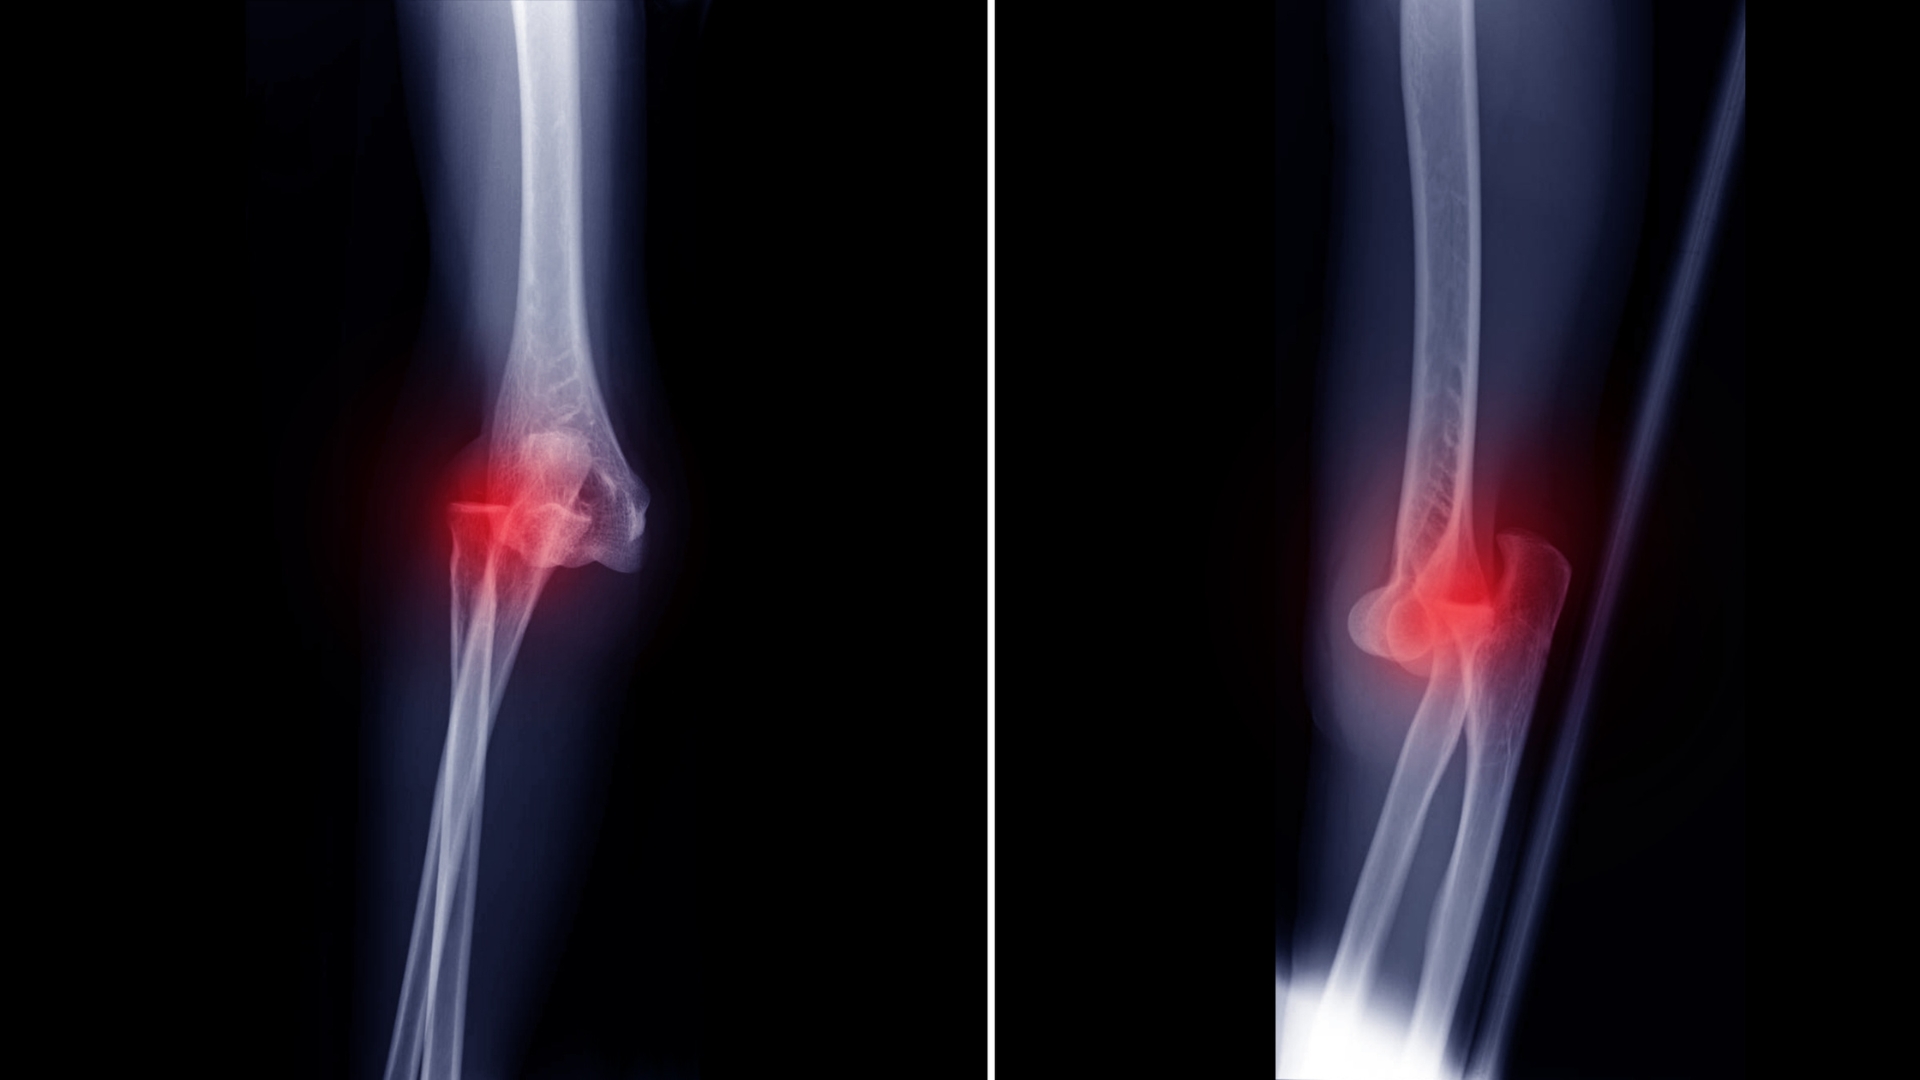

- X-quang khớp khuỷu: Chụp X-quang là phương tiện chẩn đoán cơ bản và phổ biến nhất. Hình ảnh X-quang giúp xác định rõ vị trí trật khớp, hướng trật (ra sau, ra ngoài, ra trước…), cũng như phát hiện các tổn thương phối hợp như gãy xương quanh khớp.